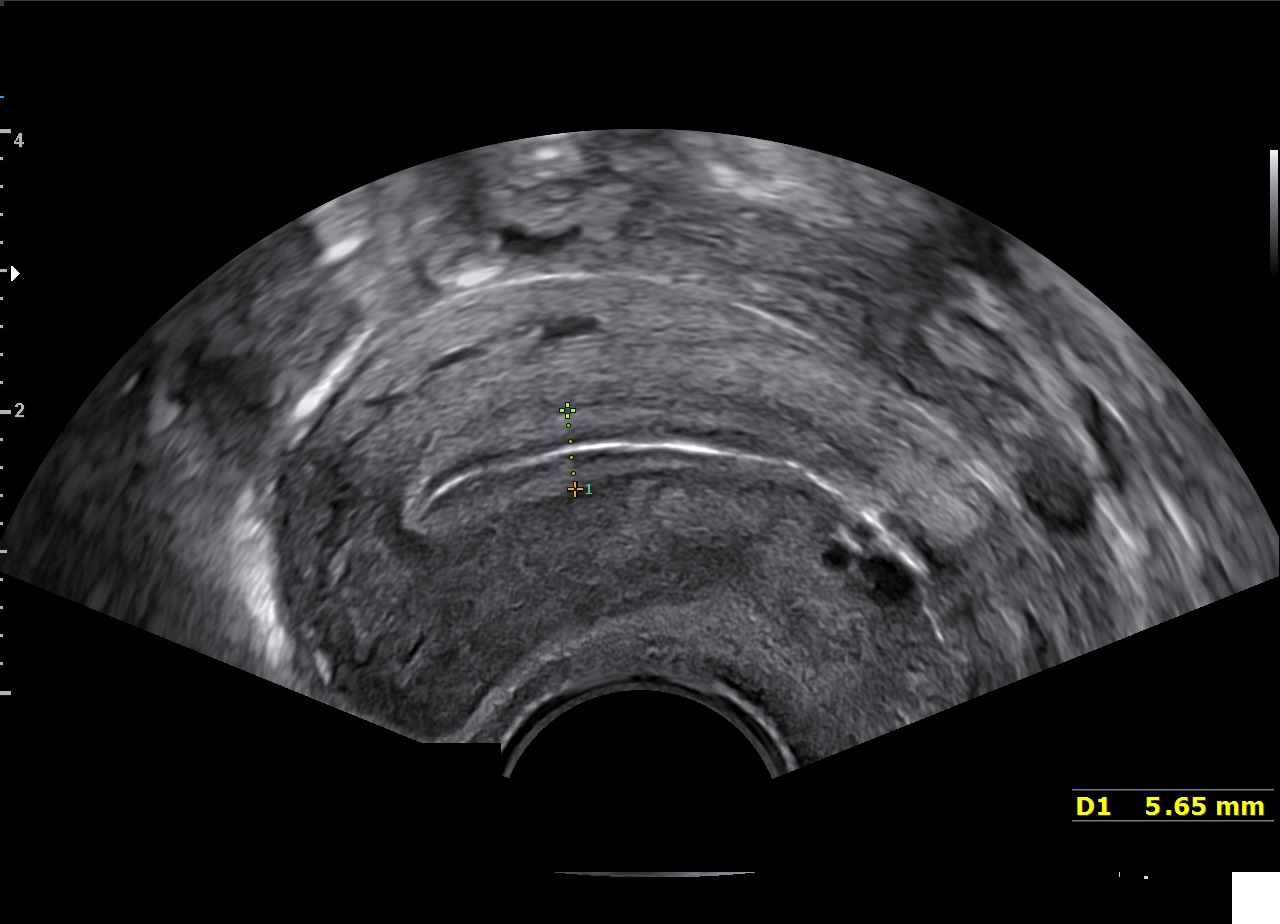

Le filtre de réduction de bruit ClearVision améliore les contours d'une structure anatomique et augmente le rapport signal sur bruit. Il permet de délivrer des images 2D plus nettes et augmente la différenciation tissulaire.